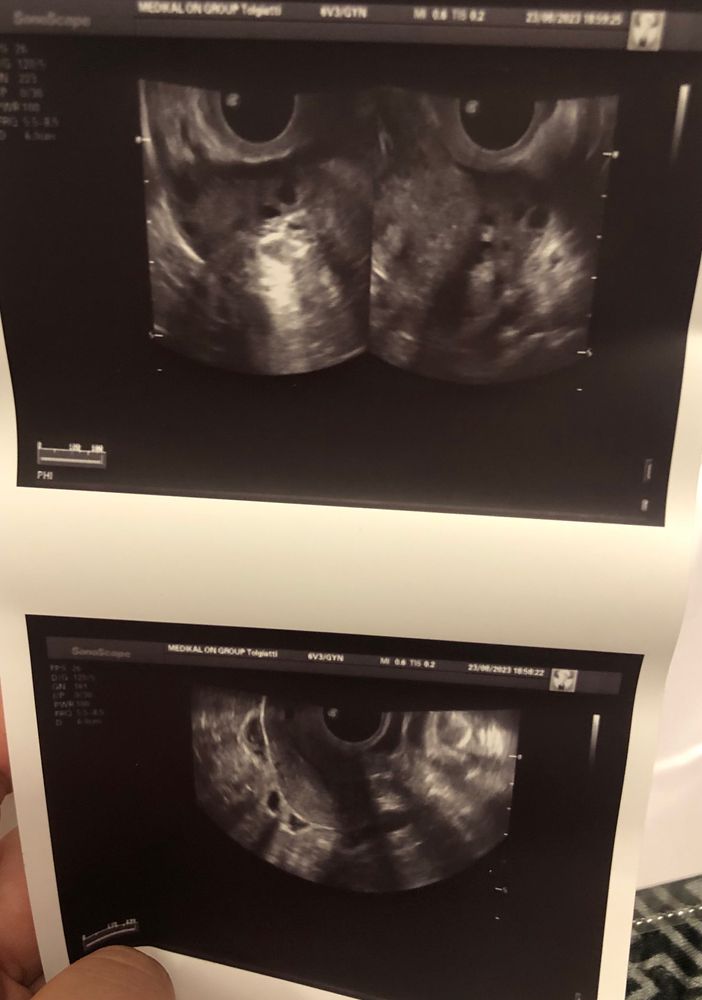

Ксюша в Зачатие 2 года Где желтое тело на узи? Фолликулометрия Делала узи и дали снимок, овуляция была, но не понимаю где желтое тело на снимке. Посмотрите еще 20 записей на эту тему Лучший ответ Алёна Я сама сегодня увидела ЖТ на УЗИ и врач сказал, да это оно Если в заключении нет, значит не увидела 24.08.2023 Ответить Ксюша Алёна, такое большое. Видимо у меня нету( 24.08.2023 Ответить Алёна Планюша , нет наоборот маленькое, 10 мм( 24.08.2023 Ответить Отменить Ответить L А вам зачем такие подробности😁 24.08.2023 Ответить Ксюша Татьяна, в заключении не написано ни слова про желтое тело. Я даже не понимаю есть ли оно вообще … 24.08.2023 Ответить 7 дпо ЖТ... Планирование второй беременности) Чаты Беременных Выберите чат: Январята-2026 Февралята-2026 Мартята-2026 Апрелята-2026 Майчата-2026 Июнята-2026 Июлята-2026 Августята-2026